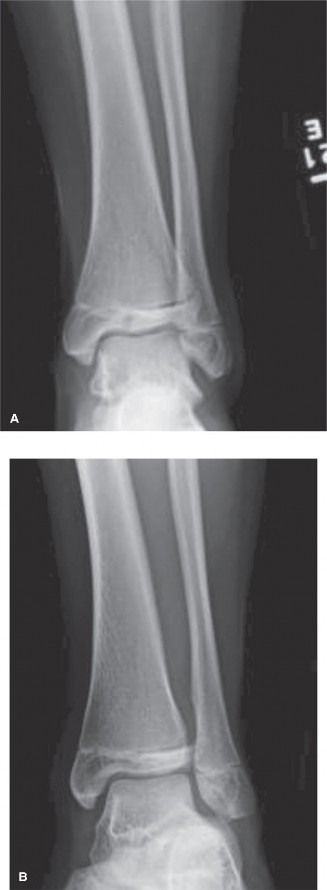

Potential for other intra-articular pathology with tibial tubercle fractures? CASE 10 You are called to the emergency room to evaluate a 13-year-old male complaining of acute right ankle pain. He reports that he injured his ankle earlier in the day when another player “took him out” during a soccer match. He was unable to bear weight through the right lower extremity and was brought promptly to the hospital for evaluation and management of his injury. An anteroposterior radiograph of the patient’s ankle is shown in Figure 10–14.

Figure 10–14

Which of the following answers correctly pairs the eponym commonly used to

describe this injury with the affected anatomic structure?

- Tillaux fracture; ATFL (anterior talofibular ligament)

- Tillaux fracture; AITFL (anterior inferior tibiofibular ligament)

- Chopart fracture; ATFL (anterior talofibular ligament)

- Chopart fracture; AITFL (anterior inferior tibiofibular ligament)

- Chaput fracture; ATFL (anterior talofibular ligament)

Discussion

The correct answer is (B). The radiograph shown demonstrates a Tillaux fracture, the eponym used to describe transitional ankle fractures in adolescents characterized by two main fragments: one fragment being the anterolateral distal tibial epiphysis and the second including the tibial metadiaphysis, the physis, and the posteromedial epiphysis. On an anteroposterior radiograph, the fracture line appears to run through the physis and exit through the epiphysis. The anatomic structure attached to this piece is the anterior inferior tibiofibular ligament (AITFL), one of the primary syndesmotic ligaments of the ankle. Chopart injuries involve the midtarsal joint. The Chaput fragment is another eponym (used more commonly in adult ankle fractures) to describe the fracture piece that remains attached to the AITFL. The anterior talofibular ligament (ATFL) is the most commonly injured structure in lateral ankle sprains.

After reviewing the patient’s radiographic imaging, you diagnose an injury involving the growth plate of the distal tibia. Which of the following answers correctly pairs the description of this injury with its associated Salter–Harris fracture classification?

- The fracture involves the physis only; Salter–Harris I or V

- The fracture exits from the physis into the metaphysis; Salter–Harris III

- The fracture exits from the physis into the metaphysis; Salter–Harris IV

- The fracture exits from the physis into the epiphysis; Salter–Harris III

- The fracture exits from the physis into the epiphysis; Salter–Harris IV

The correct answer is (D). The Salter–Harris classification system for describing fractures in skeletally immature individuals is as follows: Salter–Harris I fractures involve the growth plate only and are not usually evident on plain radiographs. This is usually a clinical diagnosis. Salter–Harris II injuries involve the physis (growth plate) and then the fracture line “exits” into the metaphysis (away from the joint).

This metaphyseal fragment is often called a “Thurston–Holland” fragment. Salter–Harris III injuries involve the physis and then the fracture exits into the epiphysis (towards the joint). The injury depicted in Figure 10–14 is a Salter–Harris III. Salter–Harris IV injuries involve the growth plate, with extension of the fracture into both the epiphysis and metaphysis. Salter–Harris V injuries are crush injuries through the growth plate that are often radiographically indistinguishable from Salter–Harris I injuries initially, but have higher rates of physeal arrest due to the increased force that produces this injury.